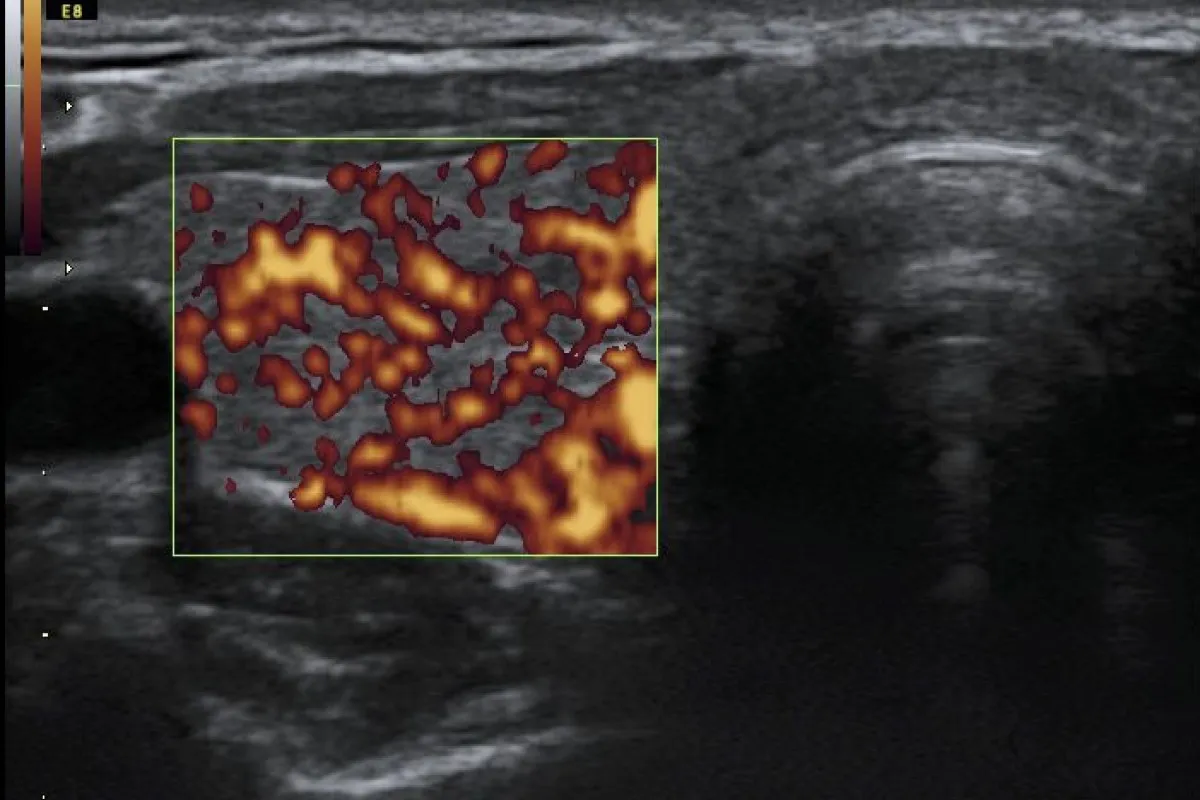

Jak już wspomniałem, podstawową przyczyną obrzęku śluzowatego jest znaczny niedobór hormonów tarczycy. Jest to stan, w którym tarczyca, niewielki gruczoł położony w przedniej części szyi, nie produkuje wystarczającej ilości tyroksyny (T4) i trójjodotyroniny (T3). Hormony te są absolutnie niezbędne do prawidłowego funkcjonowania niemal wszystkich komórek i tkanek w organizmie, regulując metabolizm, temperaturę ciała, pracę serca i układu nerwowego. Ich niedobór prowadzi do spowolnienia procesów metabolicznych, co manifestuje się szeregiem objawów, w tym właśnie obrzękiem śluzowatym.

Najczęstszym schorzeniem prowadzącym do niedoczynności tarczycy, a w konsekwencji do obrzęku śluzowatego, jest choroba Hashimoto, czyli autoimmunologiczne zapalenie tarczycy. W tej chorobie, z niewyjaśnionych do końca przyczyn, układ odpornościowy organizmu błędnie rozpoznaje komórki tarczycy jako obce i zaczyna je atakować. Prowadzi to do przewlekłego stanu zapalnego, stopniowego niszczenia gruczołu i w efekcie do trwałego upośledzenia jego funkcji, czyli niedoczynności. Jest to proces postępujący, który może trwać latami, zanim pojawią się wyraźne objawy, takie jak obrzęk śluzowaty.